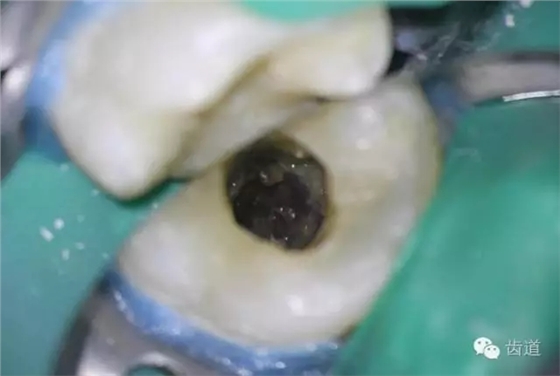

4. 初步開(kāi)髓

5. Endo-Z揭全髓室頂

6. 可見(jiàn)髓腔內(nèi)壞死牙髓組織,無(wú)滲出